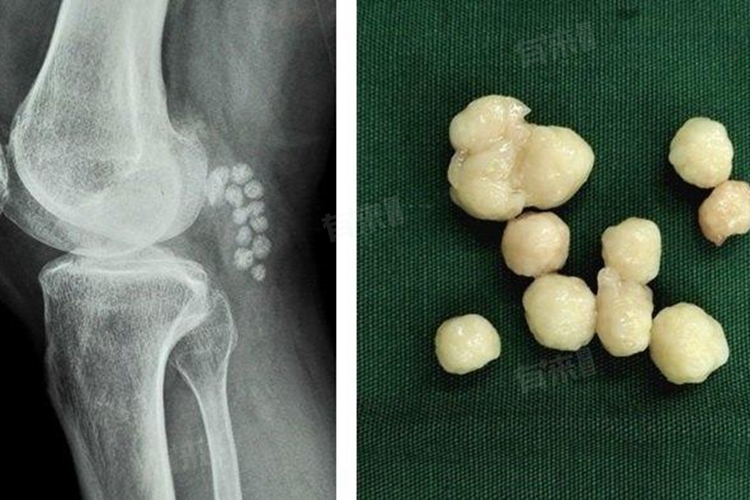

5、滑膜软骨瘤病:

- 滑膜组织化生形成软骨结节,结节脱落进入关节腔成为游离体。症状表现为关节疼痛、肿胀、弹响,可触及多个大小不一的游离体。治疗以手术切除病变滑膜和游离体为主。